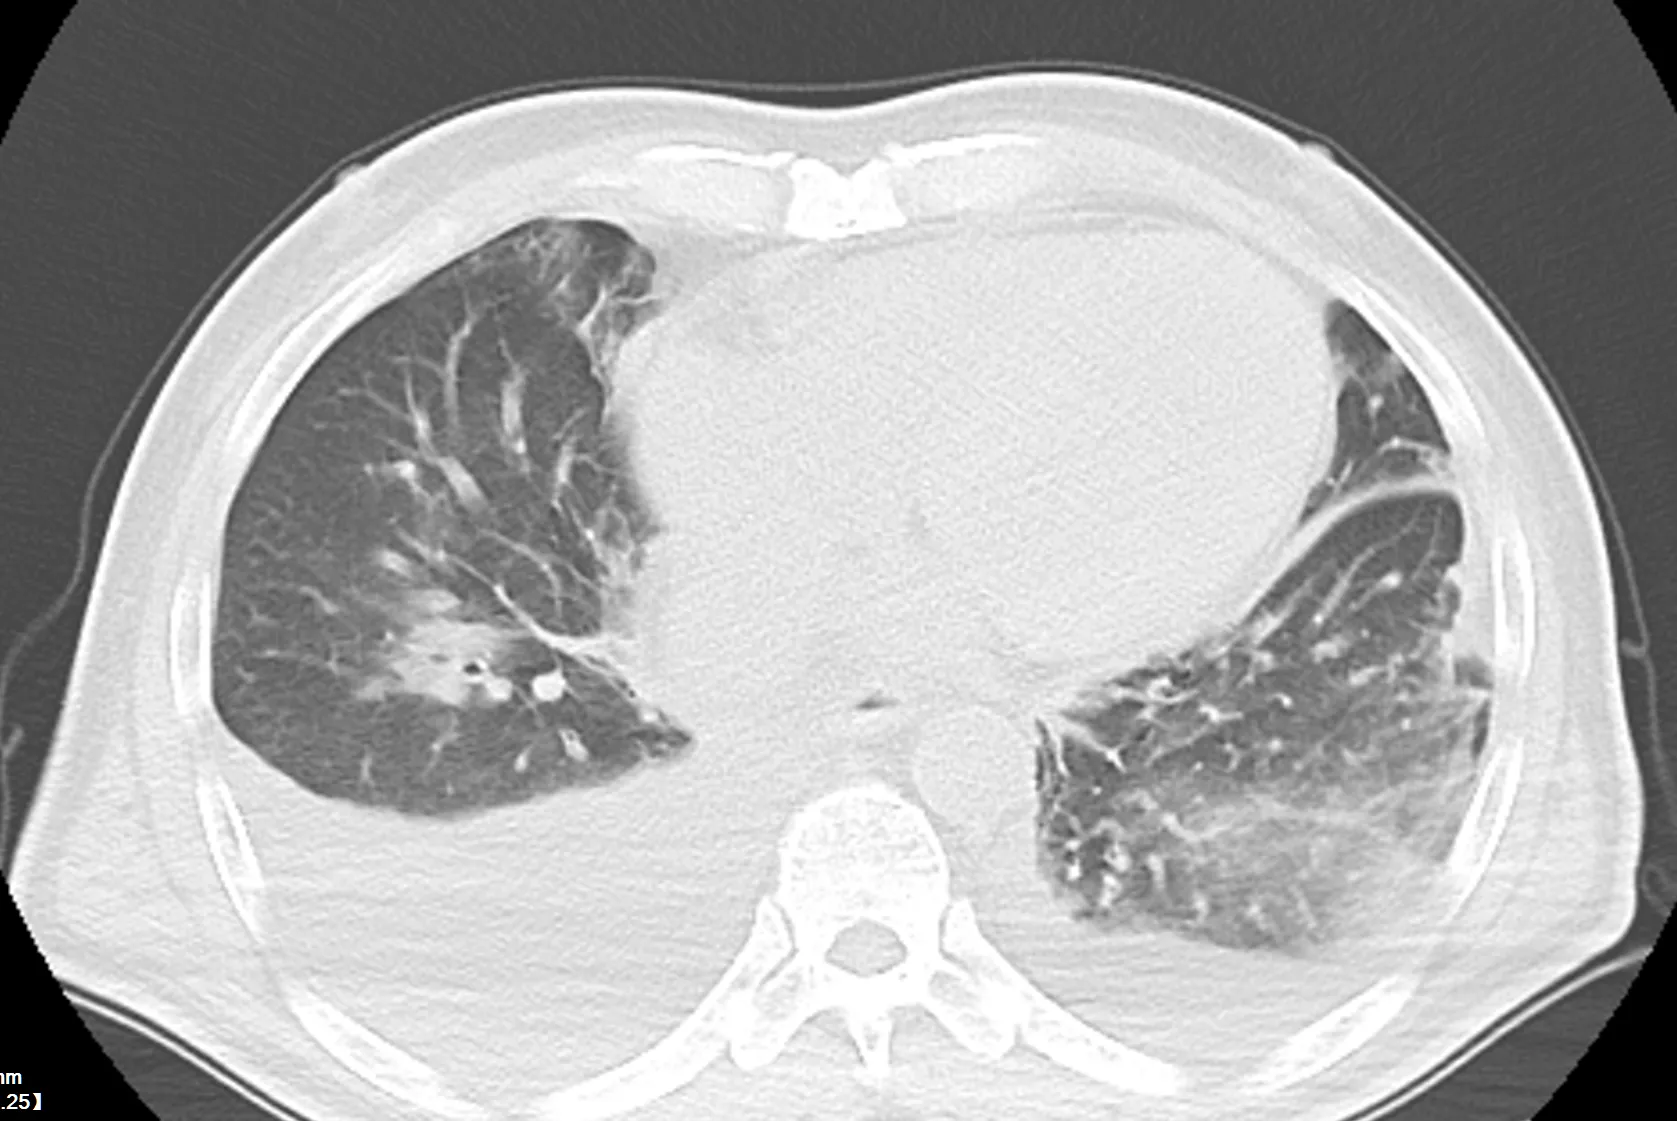

文章名称翻译过来是《磨玻璃结节 CT 随访与外科干预的 10 年生存结果比较》,主要对比了 CT 随访与直接手术切除两种临床决策在磨玻璃结节患者长期生存时间上的差异,通过统计了协和肿瘤医院过去二十年间的 684 位磨玻璃结节患者、1003 个磨玻璃结节十年间的随访结果。

(文中作者定义了磨玻璃结节为纵隔窗不可见、实性结节纵隔窗可见的相对客观的概念,但是按照这个概念,此论文中认定的实性结节按照 Fleischner 的标准仍有可能是部分磨玻璃结节)